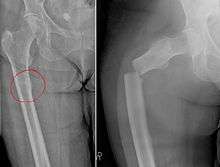

Chalkstick fracture

Chalkstick fracture due to bone metastasis of breast cancer. Left image shows the metastasis, on the right a pathological fracture a few days later.

Chalkstick fractures are fractures, typically of long bones, in which the fracture is transverse to the long axis of the bone, like a broken stick of chalk. A healthy long bone typically breaks like a hard woody stick as the collagen in the matrix adds remarkable flexibility to the mineral and the energy can run up and down the growth rings of bone. The bones of children will even follow a greenstick fracture pattern.